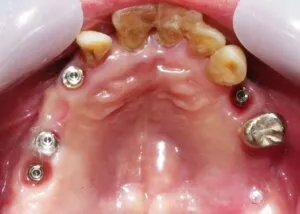

<侵襲性歯周病の難症例 / VOL.2>=治療方針

治療方針は、

⚫︎残存歯は上下顎とも全て抜歯。

⚫︎Pt.は、歯肉を模造したピンク色した補綴物は望まず、ジルコニアを希望。

⚫︎上顎は、残存歯抜歯窩骨造成術を行い、X-Guideによる待時埋入。

⚫︎下顎も同様に抜歯窩骨造成術を行い、サージカルガイドを用いた6本埋入のボーンアンカードBr、即時荷重 / all-on-6